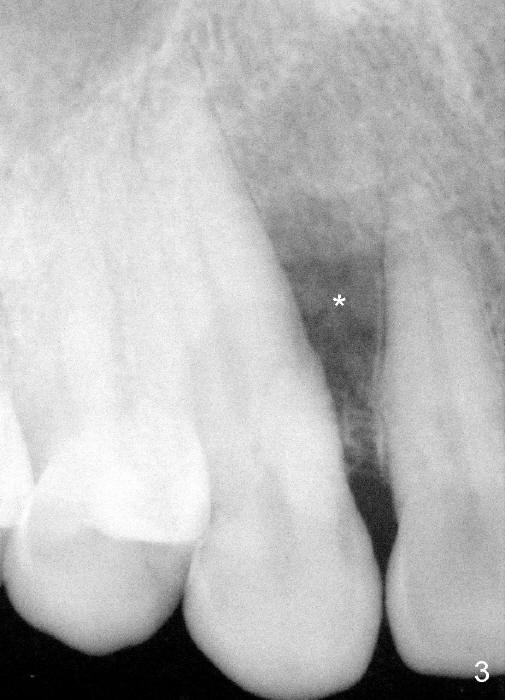

A male patient had trauma to the tooth #6 at the age of 13.  The affected tooth has remained asymptomatic for more than 30 years (Fig.1).   X-ray reveals an oblique root fracture (Fig.2 >) with radiolucency in the mesial alveolus (*, apparently normal trabecular pattern).  Six years later (Feb. 2011), an acute infection develops (Fig.4 *).  It requires incision & draining and antibiotic.  At that time, the trabecular pattern disappears around the fracture line mesially (Fig.3 *).  Four months later cone beam CT shows bone loss between #6 and 7 (Fig.5 *).  Root canal therapy is done as a palliative measure (Fig.6 R; C: Cavit).  Three months later, MTA (mineral trioxide aggregate) is placed in the coronal canal next to the fracture line (Fig.7 M).  It is hoped that MTA can promote nearby bone and cementum to regenerate to seal the fracture line.  Four months after MTA application, there is no sign of bone regeneration (Fig.8).  Bone is lost for approximately 7 mm.